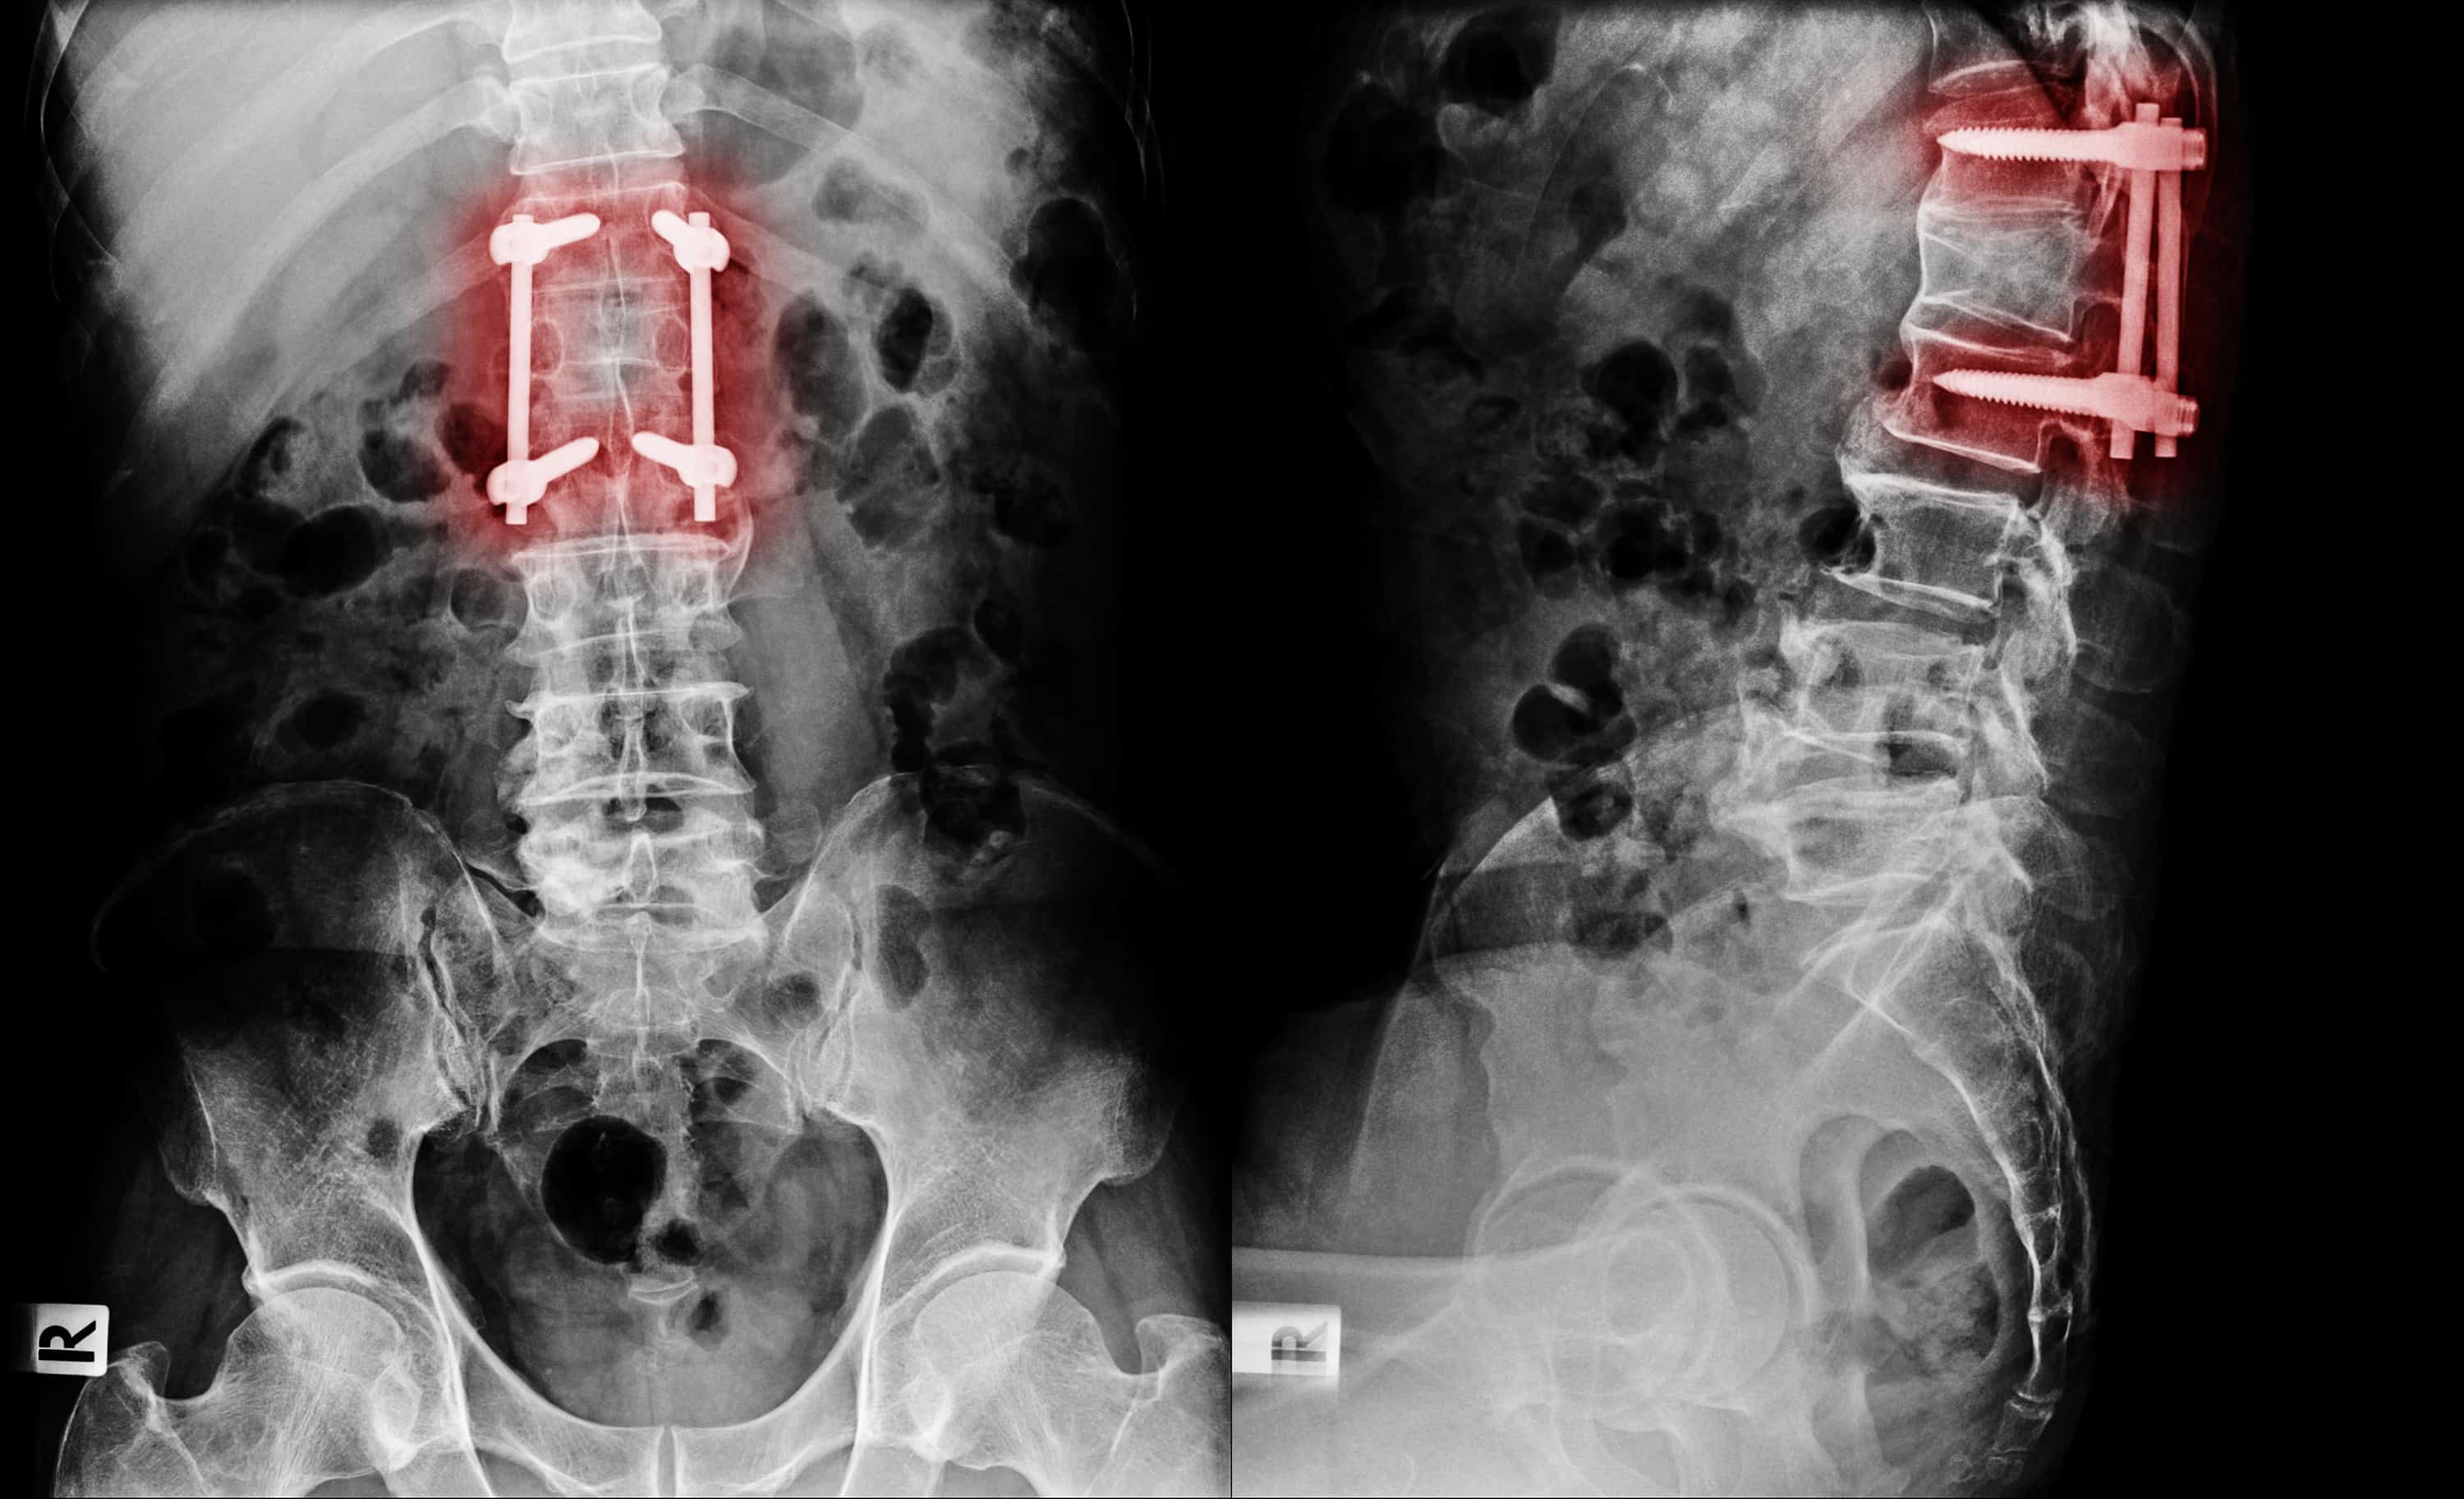

ကိုယ်ခန္ဓာရှိအဆစ်အမြစ်များအတွင်း သွေးယိုတဲ့ အခြေအနေ (Hemarthrosis) ကို ဆိုလိုပါတယ်။ ထိခိုက်ဒဏ်ရာရခြင်းကြောင့် ဖြစ်တတ်သလို ဟေမိုဖီးလျားခေါ် သွေးမတိတ်တဲ့ရောဂါကြောင့်လည်း ဖြစ်တတ်ပါတယ်။ အရိုးအဆစ်များဟာ ကိုယ်ခန္ဓာရဲ့ အစိတ်အပိုင်းတွေ ချောမွေ့စွာ လှုပ်ရှားနိုင်အောင် တည်ဆောက်ထားခြင်း ဖြစ်ပါတယ်။ အကယ်၍ အဆစ်အတွင်းကို သွေးယိုစိမ့်ခဲ့ရင် ရောင်ရမ်းခြင်း၊ နာကျင်ခြင်းတွေဖြစ်တတ်ပါတယ်။ ထိရောက်စွာ မကုသရင် အမြဲတမ်းပျက်စီးသွားနိုင်ပါတယ်။ ဘာလက္ခဏာတွေရှိသလဲ အဆစ်အတွင်း သွေးယိုတဲ့အခါ ဖြစ်နိုင်တဲ့လက္ခဏာတွေကတော့ - အဆစ်များ ရောင်ရမ်းခြင်း - နာကျင်ကိုက်ခဲခြင်း - နီရဲခြင်း - အဆစ်များကို ဖိကြည့်လျှင် လေခိုသလိုဖြစ်နေခြင်း - အဆစ်များတောင့်တင်းခြင်း - သွေးခြည်ဥခြင်း - ပုံမှန်လှုပ်ရှားနိုင်မှုမရှိခြင်း စတာတွေ ဖြစ်ပါတယ်။ ဘာကြောင့်ဖြစ်တတ်သလဲ အဆစ်အတွင်းသွေးယိုခြင်းကို ဖြစ်စေတဲ့ အကြောင်းအရာများကတော့ - ထိခိုက်ဒဏ်ရာရခြင်း၊ အရိုးကျိုးခြင်း၊ အရွတ်များစုတ်ပြဲခြင်း - ခွဲစိတ်ကုသမှုခံယူခြင်း (မှန်ပြောင်းသုံး ခွဲစိတ်ခြင်း အပါအဝင်) - သွေးယိုတတ်သောရောဂါများ (ဥပမာ ဟေမိုဖီးလျား) - သွေးကျဲဆေးများ သောက်သုံးနေခြင်း - ရောဂါပိုးဝင်ခြင်း - […]